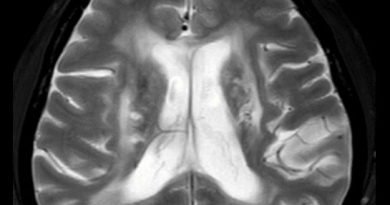

36 yaş, K

Renal transplantasyon, DM+, ateş ve nöbet

Tanınız nedir?